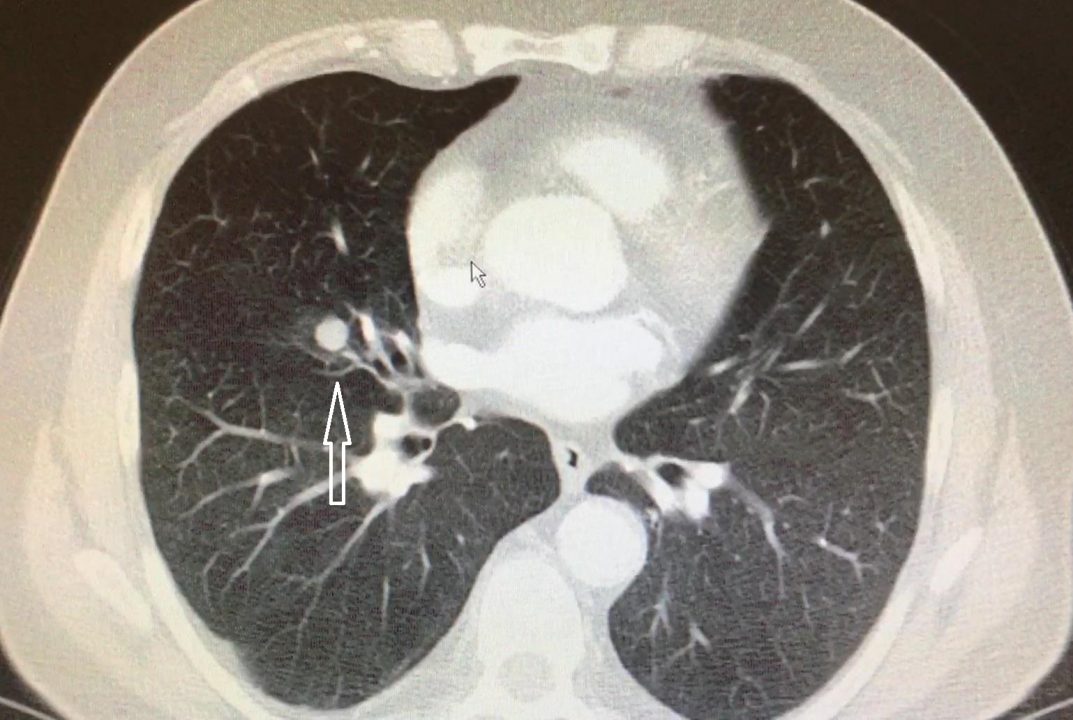

Önce nodül ne demek ona bakalım. Nodül tabir olarak, normal olmayan doku büyümesi demek. Normal olmayan büyüme deyince aklınıza hemen kanser gelmesin. Aslında cildimizdeki benlerde anormal doku büyümesi. Aynı şekilde tiroid bozuklukları olan kişilerde, guatrda nodüller sık görülüyor. Veya memede olan anormal doku büyümeleri de nodül olarak tabir ediliyor. Nodülün en önemli özelliklerinden biri, çevresindeki dokuya göre daha yoğun ve sert kıvamda olması. Eğer cilt altında ise, sert dokuyu elimizle hissediyoruz. Bazen ağrılı da olabiliyor. Gelelim akciğerdeki nodüllere; Nodül 3 cm’den küçük anormal doku büyümesi demek. Akciğerde sert kıvamlı bir nodül 1 cm’den

büyükse, hekimler olarak bizler tedirgin olmaya başlıyoruz.

Nodülün kıvamına tomografi ile karar veriyoruz. Tomografi bize radyasyon ışınları ile insan vücudunu istediğimiz kalınlıkta ve yönde dilimleyebilmemizi sağlıyor. 1 mm’den 10 mm’ye kadar. Böylece nodülü üç boyutlu olarak analiz edebiliyor, boyutunu, hacmini ve şeklini ortaya koyabiliyoruz. Bazı nodüller zatürreyi andırıyor. Bazıları ise denizkestanesini, küçük bir lastik topu veya yer elmasını andırabiliyor. Bu şekillerin hepsi bize nodülün kanser olup olmadığı konusunda fikir veriyor. 3 cm’den küçük dokulara nodül diyoruz, ama 1 cm sınırı bizim için önemli. Niye mi? Çünkü akciğer kanserini 1 cm’den küçük yakaladığımızda hastalarımızın neredeyse tamamını (%90’ın üzerinde başarı şansı var) iyileştirebiliyoruz. Bu oran 2 cm’de %80’e, 3 cm’de %70’e düşüyor. Boyut arttıkça akciğer kanserinden kurtulma ihtimalimiz tedricen azalıyor. %10 önemlidir, hele terazinin bir tarafında insan hayatı olunca daha da önemli hale geliyor.

Sigara içiyorsanız ve 55 yaşın üzerinde iseniz, akciğerinizde sert kıvamlı, kenarları düzensiz, 15 mmden büyük nodül görüldüyse, bunun kanser olma şansı %50. Sigara miktarı ve yaş arttıkça bu ihtimal daha da artıyor. Oysa sigara içmeyen ve 40 yaş altındaki kişilerde böyle bir nodülün kanser olma ihtimali %10’dan daha az… Yani sigara ve yaş karar verirken dikkate aldığımız en önemli iki kriter. Diğer önemli kriterler ailede akciğer kanseri hikâyesi, amfizem varlığı, cinsiyet, nodülün sertlik derecesi ve nodülün büyüklüğü. Hatta nodüllerin kanser riskini hesaplayan internet ve cep telefonu programları var. Makalenin başında yazdığımıza geri dönelim. Tesadüfen çekilen bir göğüs tomografisinde, 45 yaşında sigara içen bir erkekte 6 mm’lik bir nodül tespit edilirse ne yapacağız?